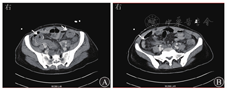

2019年10月6日立卧位腹部X线检查示右下腹部少许扩张充盈肠管影;子宫附件超声检查示盆腔积液,子宫附件区未见明显异常;泌尿系超声检查示双肾集合系分离,双侧输尿管扩张。2019年10月8日胸部CT检查示左肺上叶结节,炎性结节可能;双侧胸腔少量积液,双侧肺叶间裂略增厚,双侧胸膜略增厚。腹部和盆腔CT检查示腹盆腔积液;小肠和结肠壁弥漫性增厚;左侧肾盂、输尿管轻度扩张;腹膜后多发小淋巴结;膀胱左侧壁稍增厚,慢性炎症可能。2019年10月9日腹部增强CT检查示小肠和结肠弥漫性肠壁增厚,呈现靶征(图1A),肠系膜血管强化呈梳齿征改变(图1B),肠系膜动静脉血管未见明确栓塞征象。

放射科范新主任医师:该患者腹部CT检查示小肠和结肠弥漫性肠壁增厚,呈现靶征,肠系膜血管强化呈梳齿征改变,提示存在肠系膜血管炎;多浆膜腔积液;左侧肾盂、输尿管轻度扩张,膀胱壁局部有增厚,考虑存在慢性炎症。

风湿免疫科王红江副主任医师:患者为育龄期女性,以消化系统症状首发,同时存在多系统多脏器受累。①消化系统受累:腹部绞痛、腹泻,恶心、呕吐,急性腹膜炎体征,全腹增强CT检查示小肠和结肠肠壁弥漫性增厚,存在靶征;肠系膜血管强化呈梳齿征;考虑狼疮肠系膜血管炎(lupus mesenteric vasculitis, LMV)。②肾脏受累:多次尿常规检查示尿蛋白弱阳性,尿白细胞计数为10个/高倍镜视野,尿红细胞计数为5个/高倍镜视野。③血液系统受累:血常规检查示白细胞减少并存在贫血。④多浆膜腔积液:胸腔积液、腹水、盆腔积液。抗双链DNA抗体、抗核抗体、抗干燥综合征A抗体和抗Ro52抗体均为阳性。补体C3降低。根据1997年美国风湿病学会推荐的SLE分类标准,考虑SLE诊断明确[2]。患者以消化系统症状首发,LMV诊断明确,按照英国狼疮评估组-2004评分系统分类应属重型SLE[3]。

LMV是SLE患者出现急性腹痛的最常见原因[8],又称作狼疮肠炎。SLE患者补体激活和免疫复合物介导的血管和组织损伤是LMV发病的关键机制[9]。LMV的患病率不高,北美和欧洲地区SLE患者的LMV患病率为0.2%~6.4%,亚洲地区为2.2%~9.7%。LMV以腹痛、腹泻、呕吐为基本临床表现,如不及时给予有效治疗,可导致肠缺血伴出血、胃肠穿孔、败血症,甚至弥漫性肠坏死,病情凶险,因此尽早确诊尤为重要。靶征(肠壁增厚)和梳齿征(肠系膜血管充血)是LMV典型的CT表现[10]。以LMV首发的SLE患者,腹部症状缺乏特异性,易被误诊。实验室检查示白细胞减少、补体水平降低,应予以重视,警惕LMV可能。